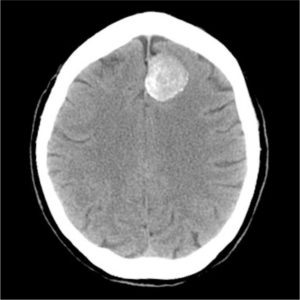

На компьютерной томограмме нашей больной действительно обнаружилось и новообразование в левой лобной доле, и зоны ишемии в других отделах головного мозга, что говорило о том, что оба моих предположительных диагноза оказались верными.

Картинка взята из интернета для представления об опухолевом процессе.

Предварительный диагноз, который я выставил на нашем этапе, был всё же "ОНМК*. Синдром моторной афазии*, синдром когнитивных нарушений"*. И в конце всё же подписал под вопросом "Neo г. м?"*